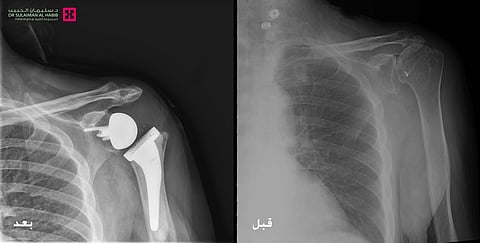

وأشار رئيس الفريق الطبي إلى أنه بعد دراسة نتائج الفحوصات والتاريخ المرضي، تم اتخاذ القرار بإجراء عملية جراحية لزراعة مفصل صناعي "معكوس" للكتف؛ موضحًا أن هذه العملية استغرقت 5 ساعات وهي الأولى من نوعها بمنطقة القصيم، وتعد من الجراحات المعقدة، وتم فيها تنظيف محيط المفصل القديم من التكلسات والزوائد العظمية المسببة للاحتكاكات، ومن ثم تركيب المفصل الصناعي الجديد المصنوع من مادة الكوبلات والكروم، والذي يتميز بجودته العالية ويساعد في تحقيق المرونة الكاملة للمفصل ومجال أكبر من الحركة والأريحية.

وقال رئيس الفريق الطبي بالمستشفى إن الجهود المبذولة تكللت بالنجاح ولله الحمد، وتم نقل المريض بعد الجراحة إلى جناح التنويم. وبعد ذلك تم البدء في تطبيق برنامج العلاج الطبيعي المكثف، ومن ثم عاد المريض إلى منزله بعد 5 أيام وهو بصحة جيدة، وقد انتهت لديه الآلام السابق ذكرها، وبدأ يمارس حياته بصورة طبيعية بعد أن استعاد كامل مرونة وحركة المفصل.